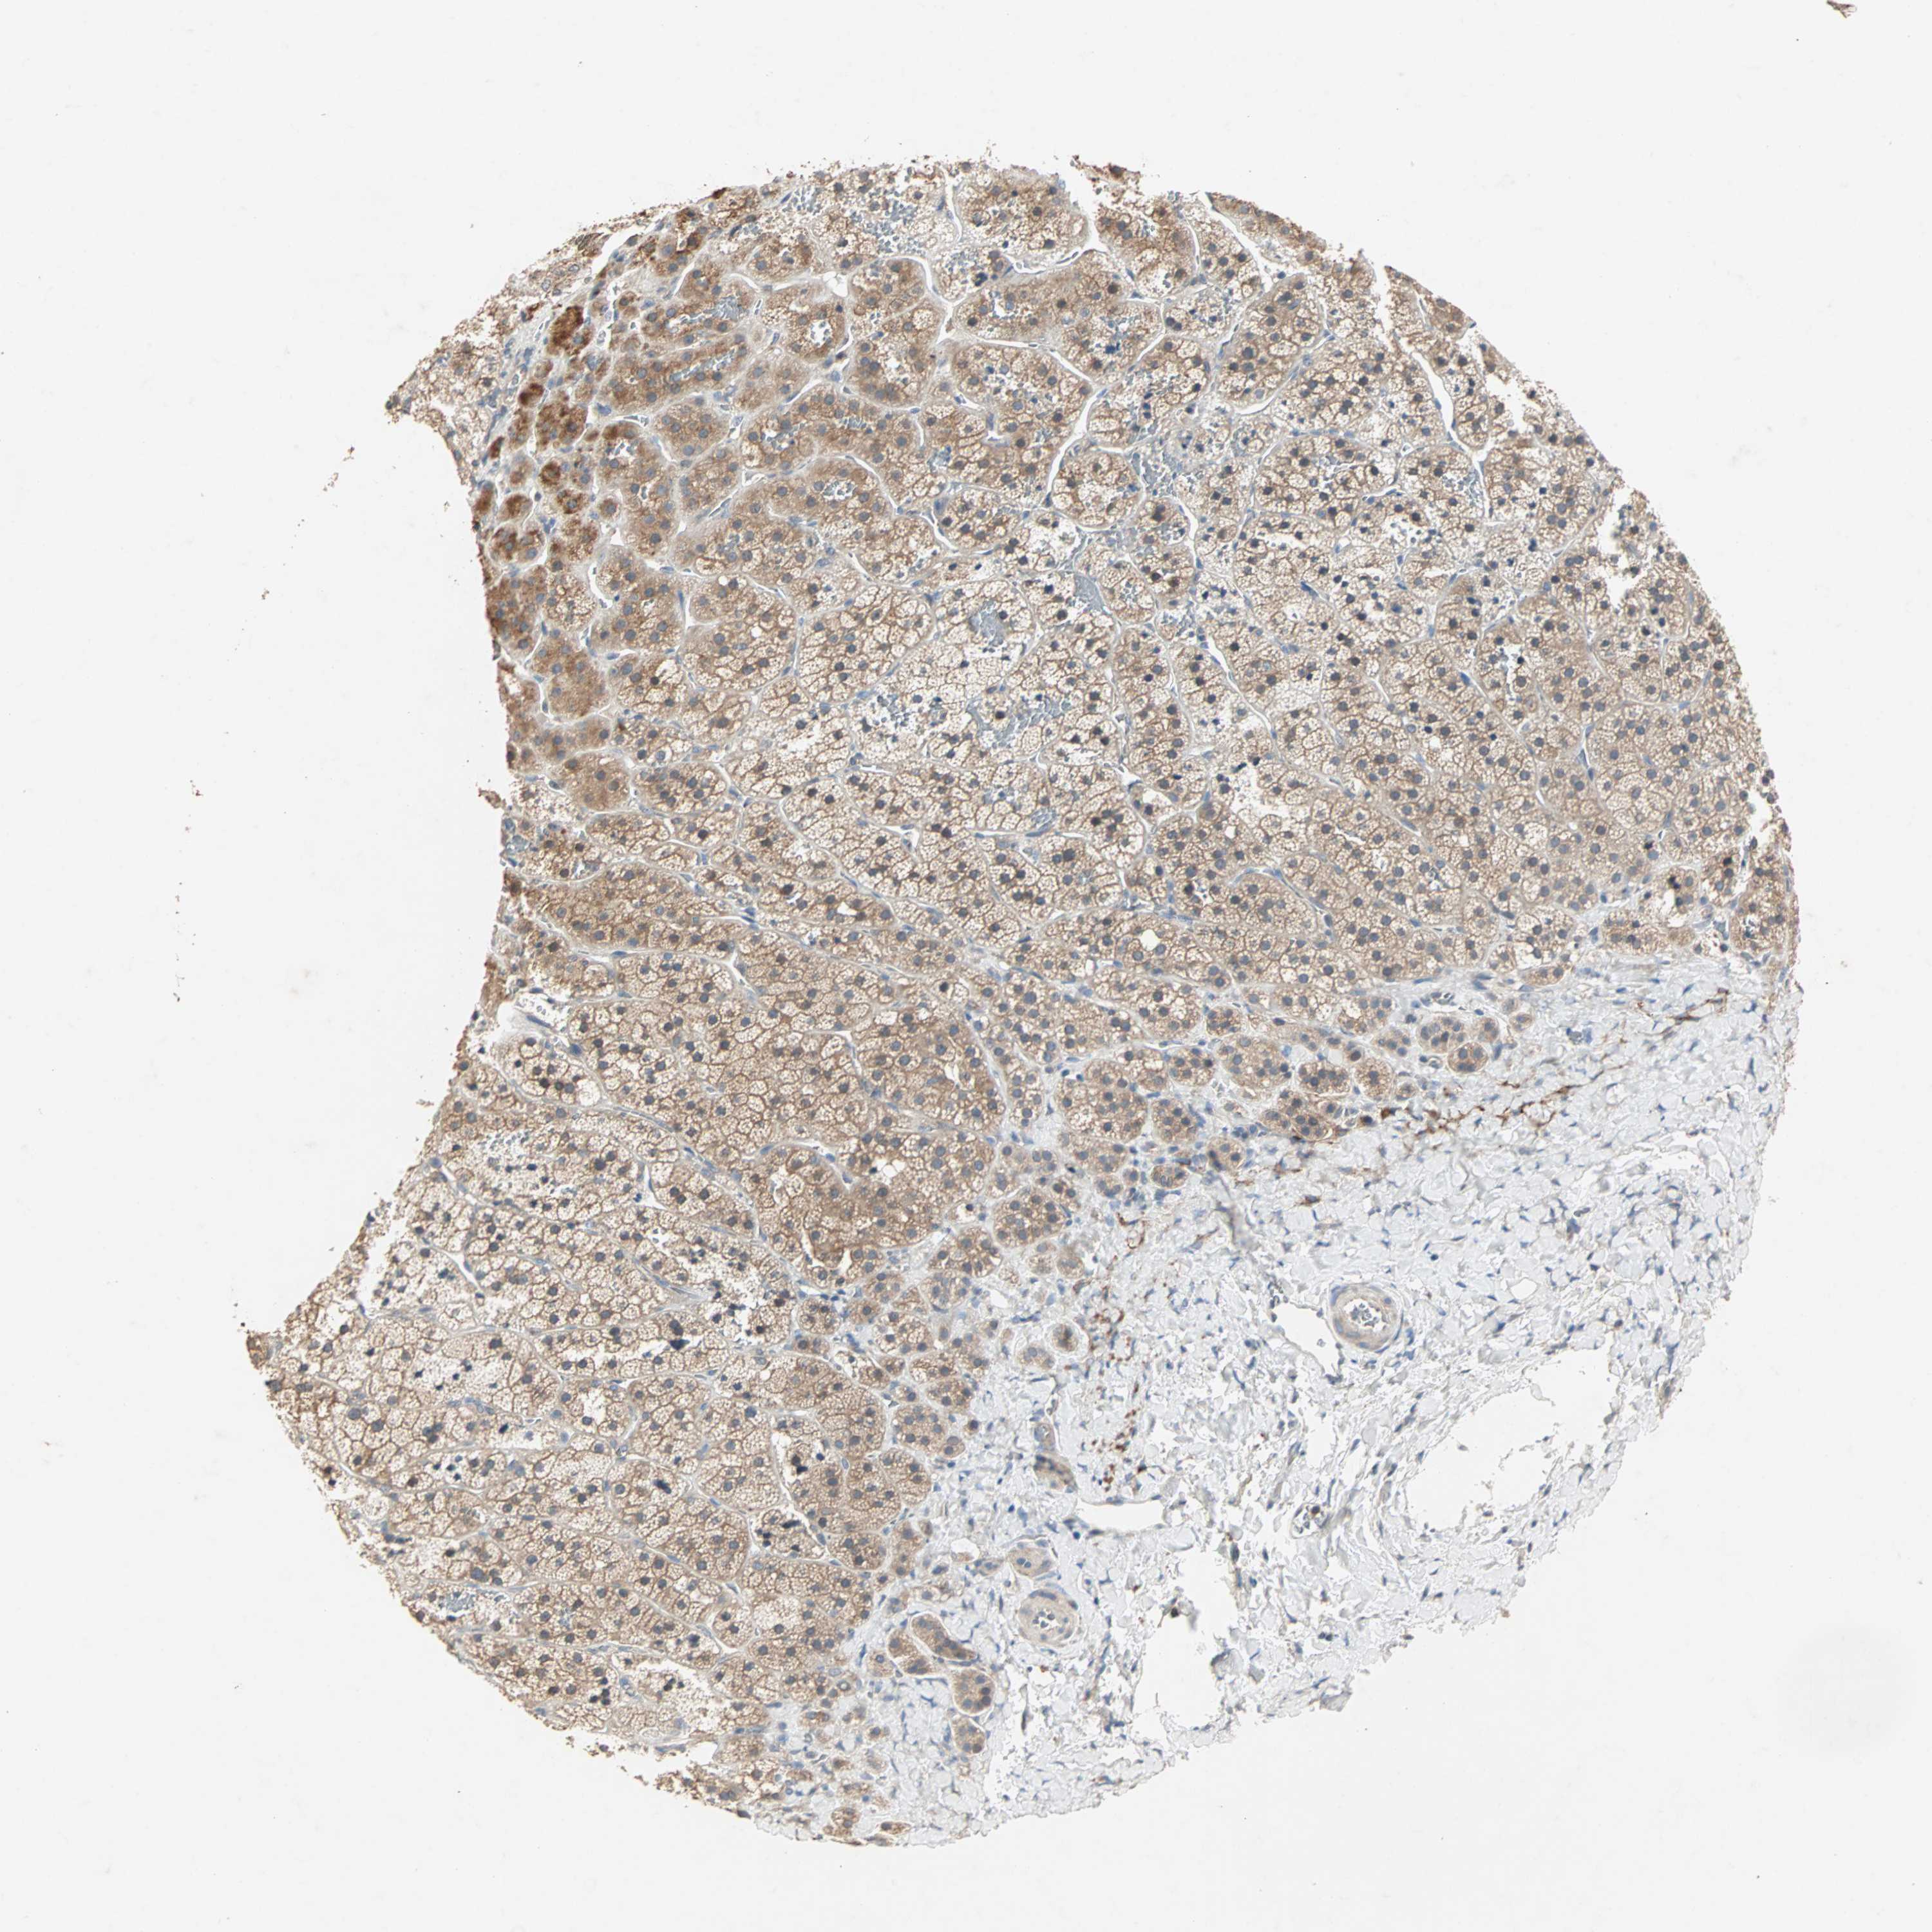

ADRENAL GLAND - Antibody stainingi

Antibody staining in the annotated cell types in the current human tissue is reported as not detected, low, medium, or high, based on conventional immunohistochemistry profiling in selected tissues. This score is based on the combination of the staining intensity and fraction of stained cells.

Each image is clickable and will lead to virtual microscopy that enables deeper exploration of all samples and also displays staining intensity scores, fraction scores and subcellular localization as well as patient and tissue information for each sample.

Antibody HPA005776

Glandular cells Medium